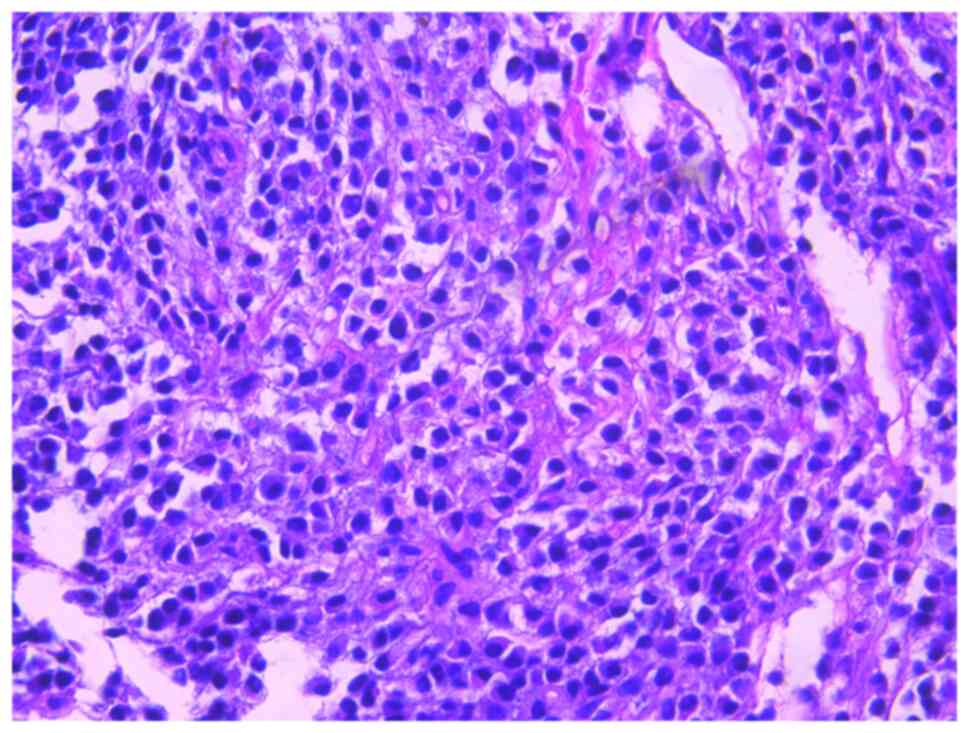

Subsequently, the patient presented with a lump around the colostomy stoma site and intermittent abdominal pain in November 2020. Physical examination revealed a lump measuring ~10×10 cm around the stoma, which did not reduce in size when the patient was lying flat. Abdominal CT (Fig. 4) revealed that the intestinal tube had protruded into the subcutaneous fat layer of the abdomen. Based on the patient's medical history, physical examination (a lump around the colostomy stoma site) and the result of abdominal CT (Fig. 4), a parastomal hernia was suspected. Surgery was the recommended treatment. Routine preoperative blood tests, coagulation function, and liver and kidney functions showed no abnormalities. Parastomal hernia repair surgery was performed using the keyhole technique in November 2020. A relatively soft drainage tube was placed subcutaneously in the surgical area. The patient recovered well after the surgery and was discharged on the third postoperative day without removing the drainage tube. During discharge, the surgical area was not compressed. However, five days after discharge, the patient experienced swelling, pain and bleeding at the surgical site. Abdominal CT showed a hematoma in the surgical area (Fig. 5). After taking hemostatic treatment measures (hemostatic drugs, compression hemostasis), fresh blood still slowly flowed out from the drainage tube. Dynamic reexamination of coagulation function showed that it gradually deteriorated, and the activated partial thromboplastin time was gradually delayed to 60 sec, which was 20 sec longer than normal (reference range, 20–40 sec). The patient had stubborn anemia, and after multiple blood transfusions, no significant increase was identified in hemoglobin, which remained between 45–68 g/l (normal range, 130–175 g/l). A bone marrow biopsy was also performed to investigate the cause of persistent bleeding (Fig. 6). The bone marrow smear was stained using the Wright staining method and 200 cells were counted under a microscope. The results showed abnormal proliferation of plasma cell lines in bone marrow smears, accounting for 35% of total cells, with an immature plasma cell composition accounting for 21.0% of total cells (normal range, 0–0.8%). This result is consistent with the diagnosis of multiple myeloma (10,11). Fig. 6 shows the characteristics of abnormal plasma cells: This type of cell was significantly different in size, with the cell body and nucleus appearing circular, elliptical, ovoid or irregular in shape. The nucleus was misaligned, the chromatin of the nucleus appeared as a granular or loose network and certain cells showed obvious nucleoli. The cytoplasm was rich, stained opaque dark blue and flame-like, with obvious light staining bands around the nucleus. Nodular protrusions and vacuoles were easily observed, while no particles were seen. The morphological features were consistent with those of MM (10). Further testing revealed elevated serum immunoglobulin A (IgA) levels of 76.7 g/l (normal range, 0.82–4.53 g/l) and significantly increased serum β2 microglobulin (β2-microglobulin) levels of 16,205 ng/ml (normal range, 604–2,286 ng/ml). Based on the results of the bone marrow puncture, the bone destruction, anemia and bleeding were attributed to MM. After consultation with a hematologist, the patient was diagnosed with MM (IgA-λ type, Durie-Salmon Stage III). The Durie-Salmon staging system is a classic staging system for MM. The staging criteria for Stage III are as follows: One or more of the following abnormalities must be present: Hemoglobin <8.5 g/dl; serum calcium >12 mg/dl; very high myeloma protein production; IgG peak >7 g/dl; IgA peak >5 g/dl; Bence Jones protein >12 g/24 h; and >3 lytic lesions on bone survey (11). The patient was transferred to the hematology department and was treated with the PCD regimen (bortezomib, cyclophosphamide, dexamethasone), chemotherapy and blood transfusion. The specific dosage of medication is calculated based on the patient's body surface area. One chemotherapy cycle is 4 weeks and this patient received 6 cycles of chemotherapy. Afterwards, the patient received maintenance treatment with bortezomib monotherapy. The seventh rib lesion invaded the surrounding soft tissue, and the interventional department performed an empty needle puncture biopsy on it. The pathological and immunohistochemical results of the puncture tissue are consistent with multiple myeloma (10). The lesion was determined to be plasmacytoma, suggesting involvement of MM (Fig. 7), and the immunohistochemical results were as follows: CD138 (+), CD38 (+), cytokeratin (CK) (−), Ki67 (15%, +), Lambda (+) and MM oncogene 1 (+) (Fig. 8). CK negativity indicated the absence of malignant cells of epithelial origin. The patient's condition gradually improved, with increasing hemoglobin levels, recovering coagulation function, absorption of the hematoma around the stoma (Fig. 9) and alleviation of bone pain. For the past 2 years, the patient has been regularly treated in the hematology department and the progression of the MM has been slow (Figs. 10 and 11). Fig. 10 is a PET/CT image of the patient diagnosed with MM one year later. The arrows in Fig. 10 indicate the metabolic status of the lesionsin the right seventh posterior rib, upper sternum, and first lumbar spine. The increased metabolism of these three main lesions is consistent with the manifestation of MM. In Fig. 11, row A represents the situation of lesion in the upper sternum at different time-points; row B shows the situation of lesion in the upper sternum at different time-points; and row C shows the situation of lesion in the upper sternum at different time-points. The arrows in Fig. 11Aa, Ba and Ca refer to the lesions of the upper sternum, the seventh rib on the right side and the first lumbar vertebra when MM was diagnosed. Fig. 11Ab-Cb shows the respective lesions 1 year after the diagnosis of MM and Fig. 11Ac-Cc shows them at 2 years after the diagnosis of MM. After comparison, the progression of these three lesions was not obvious. After treatment, the soft tissue mass around the lesion of the right seventh rib gradually became smaller. The patient has not experienced any worsening bone pain symptoms since being diagnosed with MM. The patient has been regularly visiting the hematology outpatient department. During the follow-up period, the patient's blood routine, coagulation function and serum immunoglobulin are being tested every two months, and chest CT and spinal CT examinations conducted every 6 months. During follow-up, there has been occasional mild anemia but no coagulation abnormalities.

Figure 6.

Image of bone marrow puncture smear (magnification, ×1,000). Abnormal proliferation of plasma cell lines; plasma cells vary in size; nuclear translocation; plasma cells are circular, elliptical or irregularly shaped; the cytoplasm is blue and the nucleus is deep purple; perinuclear light staining; erythrocyte rouleaux formation.

Figure 7.

Pathological image of pleural lesion (magnification, ×400; hematoxylin and eosin stain).